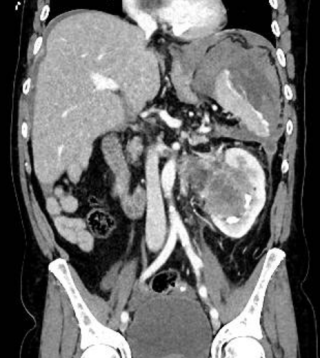

A 31-year-old previously healthy woman, with no surgical history, presented with sudden-onset, severe peri-umbilical abdominal pain unresponsive to high-dose opioids. CT-scan revealed mildly dilated distal jejunum with mesenteric edema and free fluid (Fig. 1, 2). Because of persistent pain despite step III analgesia, emergency diagnostic laparoscopy was performed. Intraoperatively, a closed-loop obstruction of an ileal segment was identified, herniated through a narrow internal window formed by an adherent mesenteric vessel supplying a Meckel’s diverticulum (Fig. 3). The vascular band was divided, releasing the closed loop, with no irreversible small bowel ischemic damage. The Meckel’s diverticulum was resected. The post-operative course was uneventful, and the patient was discharged after two days.